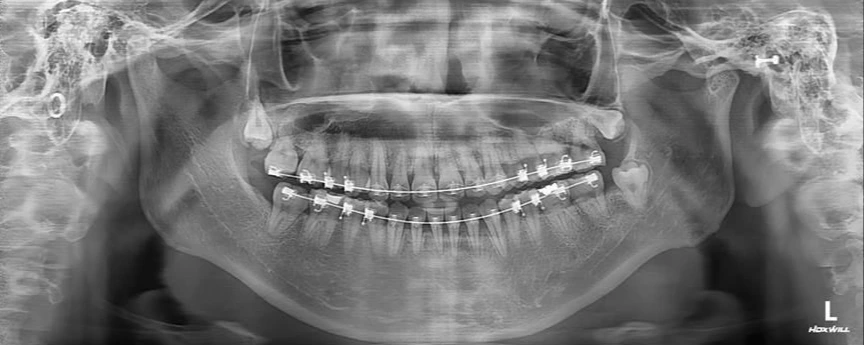

슬라이드110.JPG 좌측의 턱관절이 녹아 있어서 우측에 비해 짧다.

이 환자의 X-ray 상에서 좌측의 턱관절이 우측에 비해 짧은 것을 알 수 있다.

"대부분의 안면비대칭은 턱관절 질환으로 턱관절이 녹아서 생긴다.

성장 과정 중에 턱관절이 아프고 불편한 시기가 있는 경우도 있지만, 턱관절 질환이 서서히 생겨서 환자가 턱관절이 아프다는 것을 느끼지 못하는 경우도 많다.

따라서 이런 안면비대칭을 치료하기 위해서는 반드시 턱관절 질환이 현재도 진행 중인지 여부를 확인하여야 한다"

다행히 이 환자는 턱관절이 현재는 건강해서 양악수술을 통해서 안면비대칭을 치료할 수 있었습니다.